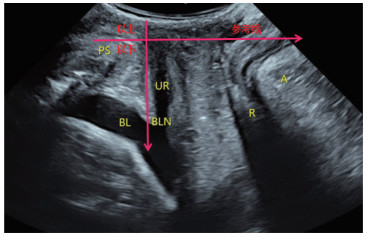

1.2.2.2 操作方法经阴道超声观察盆底结构,膀胱适度充盈,取截石位,充分暴露会阴部,将耦合剂涂抹于探头表面,用探头套包裹探头,将探头轻置于会阴部;显示盆底矢状切面图像,见图 1。观察耻骨联合(pubic syphilis,PS)、尿道(urethra,UR)、膀胱(bladder,BL)和膀胱颈(bladder neck,BLN)。在二维测量2组孕妇膀胱颈位置(D)、尿道倾斜角(β)、膀胱尿道后角(poster urethrovesical angle,PUVA),分别测量静息及张力状态下膀胱颈位置(D1、D2)、尿道倾斜角(β1、β2)、膀胱尿道后角(PUVA1、PUVA2),并计算膀胱颈移动度(bladder neck descent,BND)、尿道旋转角度(urethra rotation angle,URA)。在静息及张力状态下启动三维成像,获取肛提肌裂孔面积(levator hiatus area,LHA),见图 2,测量2组孕妇不同状态下LHA(LHA1和LHA2)。

| PS, pubic syphilis; UR, urethra; BL, bladder; BLN, bladder neck; R, rectum; A, levator ani muscle. 图 1 首次妊娠组经盆底超声女性盆底矢状切面 Fig.1 sagittal section of the pelvic floor of a woman the first pregnancy group |